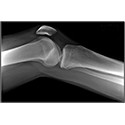

LOWER LIMB

Interactive Radiology